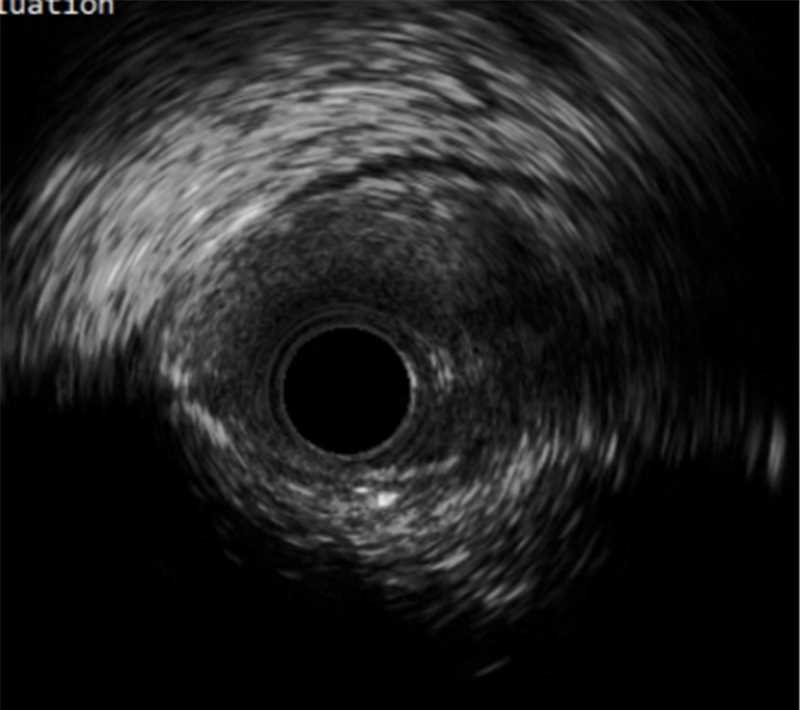

远端导丝位于真腔内;中段可见夹层及血肿;CTO段部分位于假腔

(2)在实际操作过程中,冠脉CTA可以协助评估血管形态,导丝对吻、Knuckle技术、Carlino技术、导丝升级则可以帮助导丝前进,同时联合应用血管内超声检查可以明确管腔和导丝的位置关系。